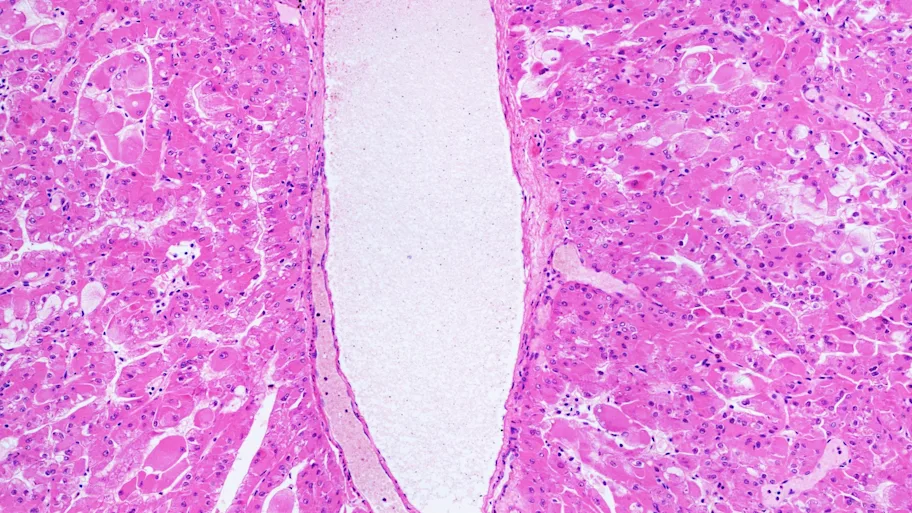

Image credit: unterwegs / Shutterstock.com